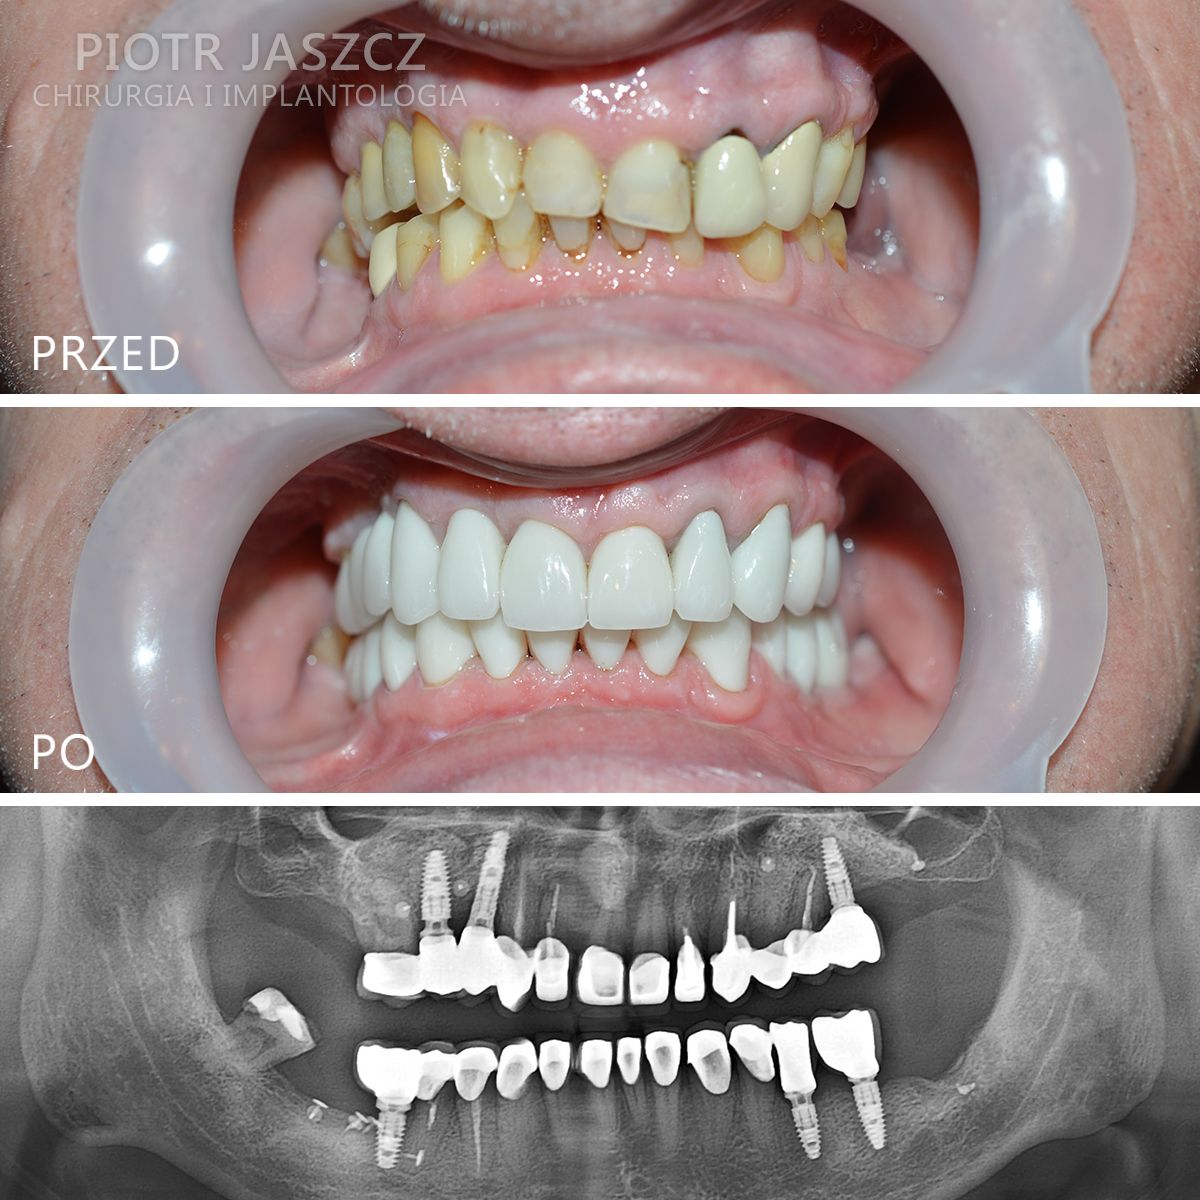

Specjalizuje się głównie w skomplikowanych odbudowach implantologicznych pacjentów bezzębnych oraz w zaawansowanych regeneracjach kostnych w leczeniu implantologicznym metodami przeszczepów kości własnej, jak również w przeszczepach tkanek miękkich w celu regeneracji dziąsła przy zębach lub przy implantach.

Wykonuje zabiegi odtworzenia zębów w 24h, polegające na usunięciu wszystkich zębów w szczęce lub żuchwie, wszczepieniu implantów metodą All-on-4 lub All-on-6 oraz oddaniu mostów na wszczepionych implantach w 24h. Metamorfozy szczęki w 24h.